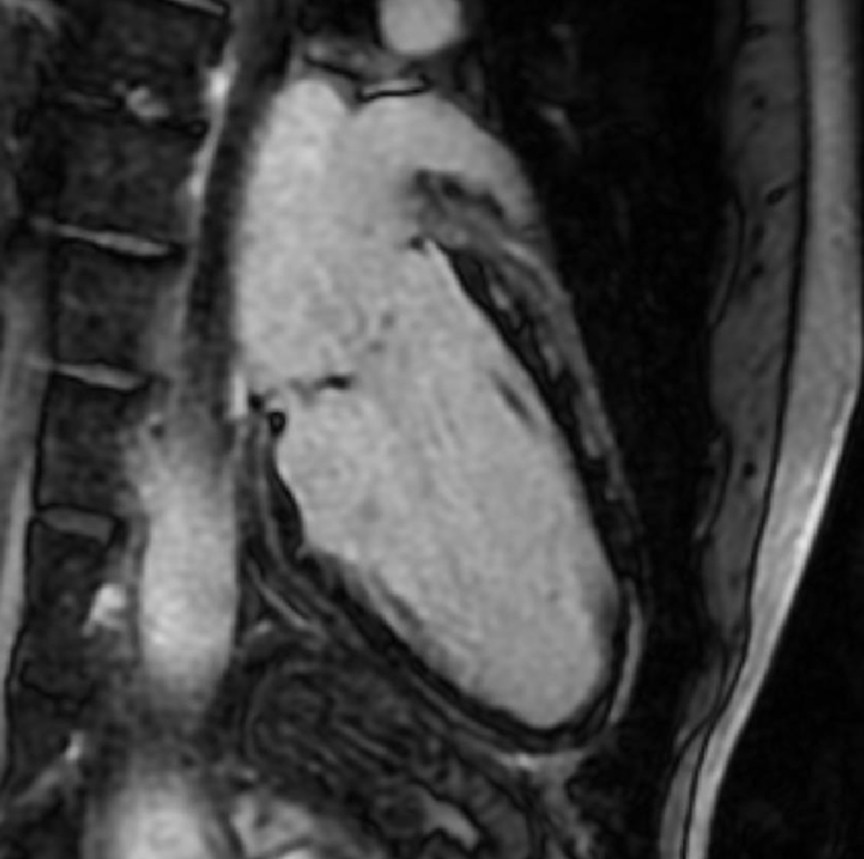

La velocità di progressione della fibrosi cardiaca: un nuovo orizzonte

La velocità di progressione della fibrosi cardiaca emerge come un nuovo e cruciale indicatore prognostico nella cardiomiopatia ipertrofica. Un recente studio evidenzia come l’LGE rate sia più predittivo degli eventi avversi rispetto alla semplice estensione della fibrosi, aprendo nuove prospettive per il monitoraggio e la gestione terapeutica dei pazienti.